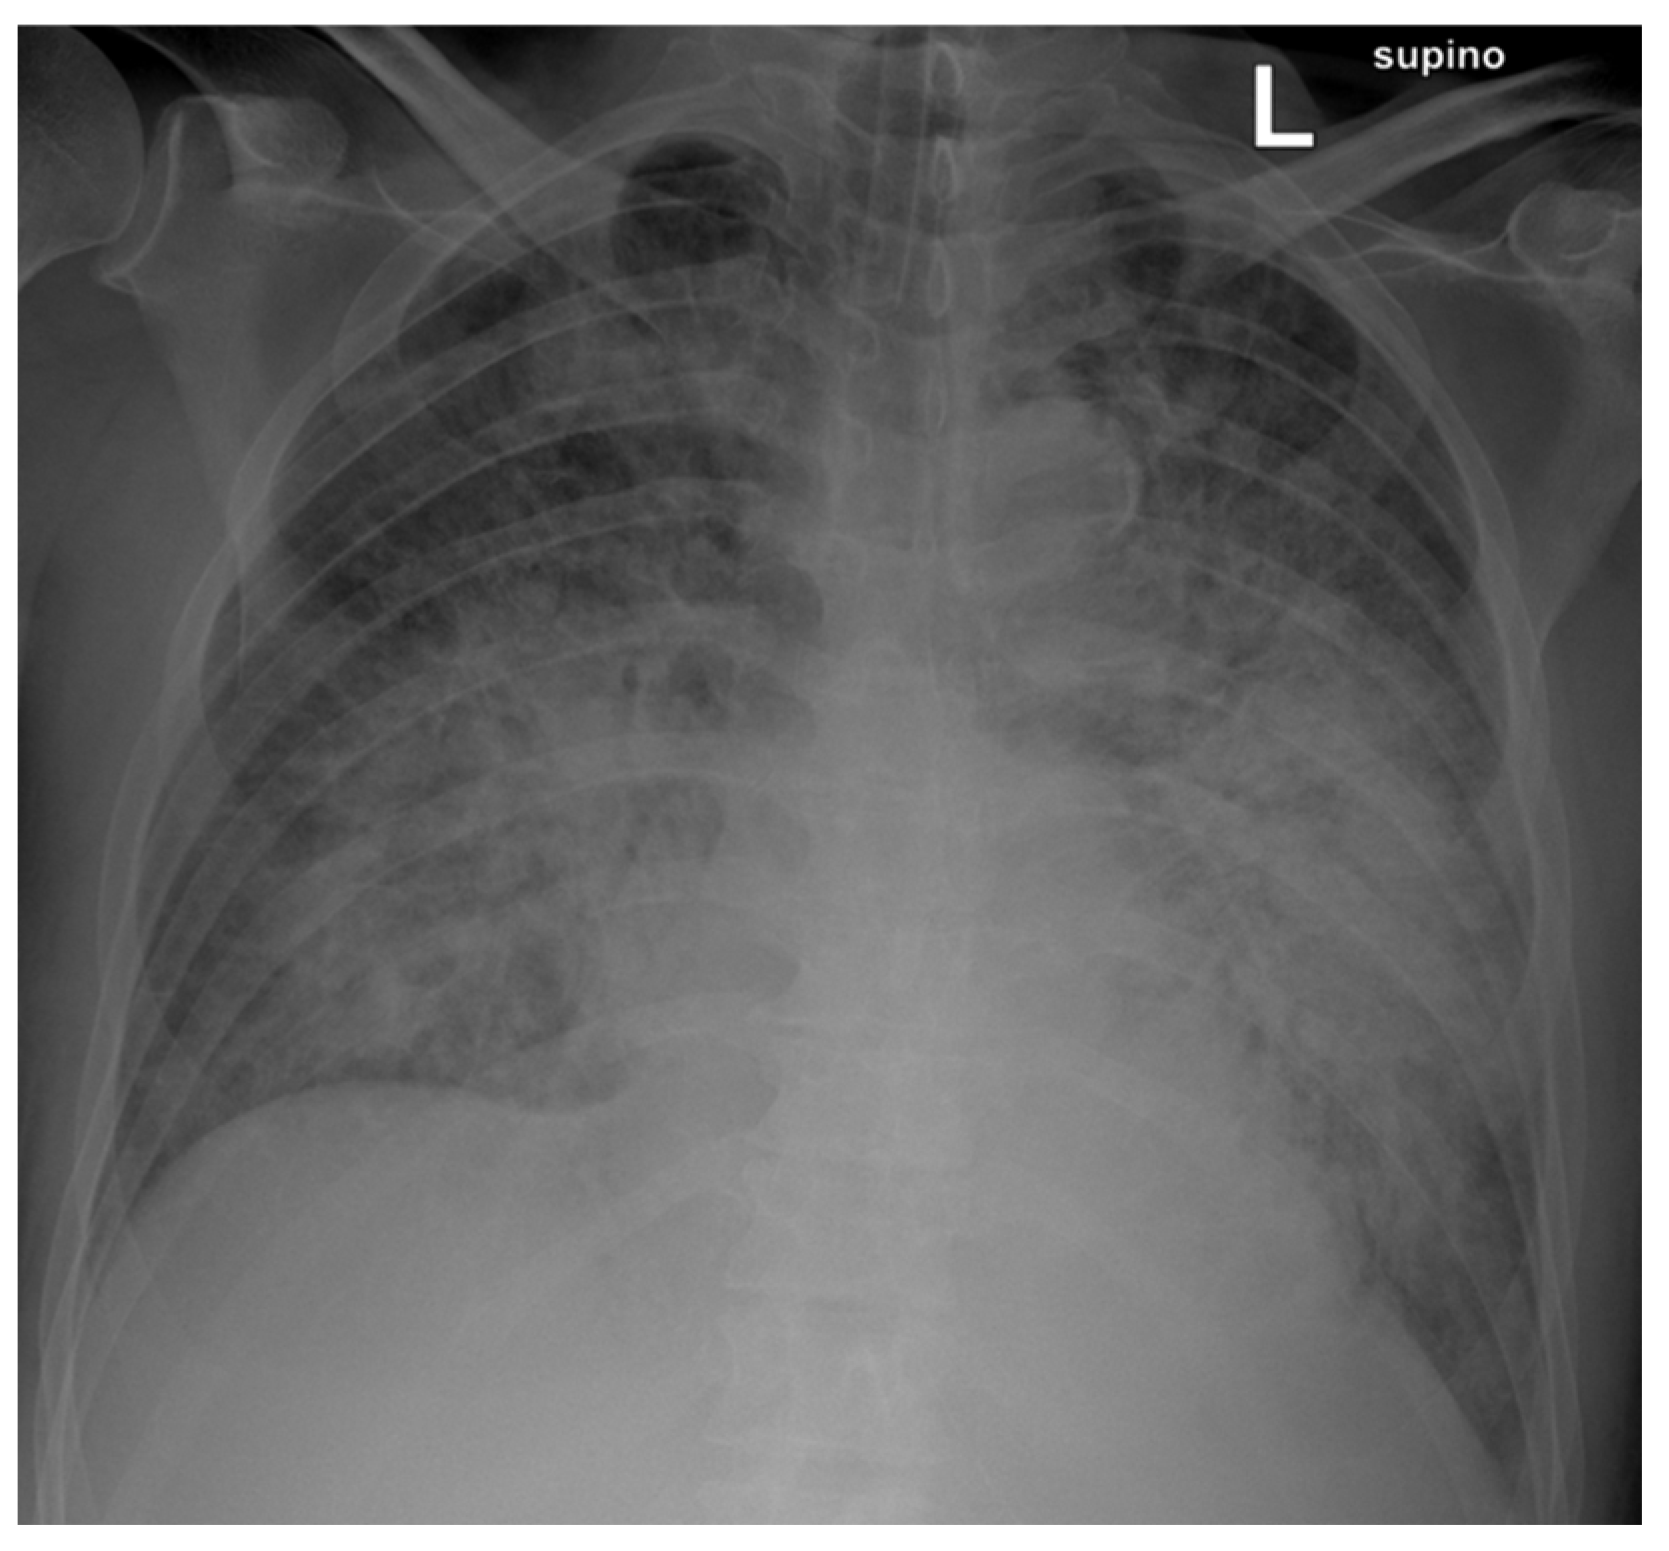

Two days after admission, the patient was transferred to the intensive care unit due to acute pulmonary edema and consequent worsening respiratory dynamics and underwent intubation and mechanical ventilation. Levofloxacin 750 mg was empirically administered for pneumonia (Figure 1).

Figure 1.

Chest X-ray shows multiple bilaterally diffused areas of predominantly perihilar interstitial–alveolar involvement, with near-complete opacification of both lungs.